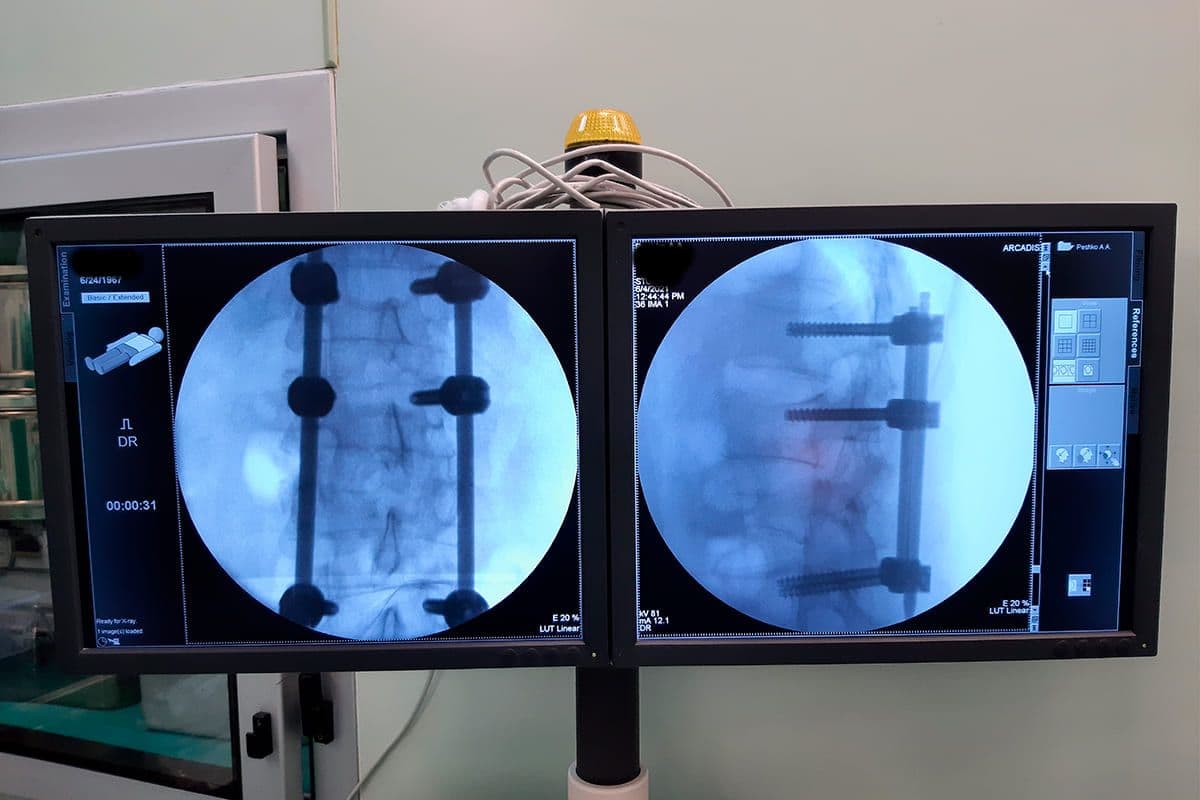

Для этих целей в РНПЦ ТО был разработан метод малоинвазивного хирургического лечения пациентов с повреждениями и заболеваниями грудного и поясничного отделов позвоночника с применением чрескожного транспедикулярного фиксатора позвоночника и кооперации с отечественным производителем «Медбиотех» подготовлена конструкция нового поколения на основе полиаксиального транспедикулярного винта с двойной фиксацией с необходимым монтажным инструментарием. Суть метода заключается в установке транспедикулярных винтов через небольшие разрезы кожи в проекции межпозвонковых суставов, позволяющие через разведенные мышечные волокна визуализировать точки введения винтов, при этом минимально травмируются сосуды и нервы. После установки всех винтов через дополнительные разрезы устанавливаются штанги, последние плотно фиксируются в головках винтов после выполнения при необходимости тракции по оси штанг.

Малоинвазивная(чрескожная) методика является достаточно эффективным методом хирургического лечения изолированных оскольчатых переломов грудопоясничного отдела позвоночника. Позволяет снизить кровопотерю во время операции, исключить необходимость выполнения широкого хирургического доступа, денервацию и деваскуляризацию паравертебральной мускулатуры, что в свою очередь сказывается на функциональном состоянии мышц в послеоперационном периоде, уменьшая болевой синдром и давая возможность начать реабилитацию в максимально ранние сроки. Используемая конструкция и монтажный инструментарий удобны в обращении и позволяют помимо жесткой фиксации поврежденного сегмента успешно выполнять репозиционные мероприятия.